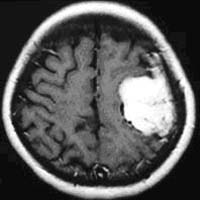

(4)髄膜腫

血管に富んだ腫瘍に対して、手術前に腫瘍を栄養する血管に対して塞栓術を施行しています。